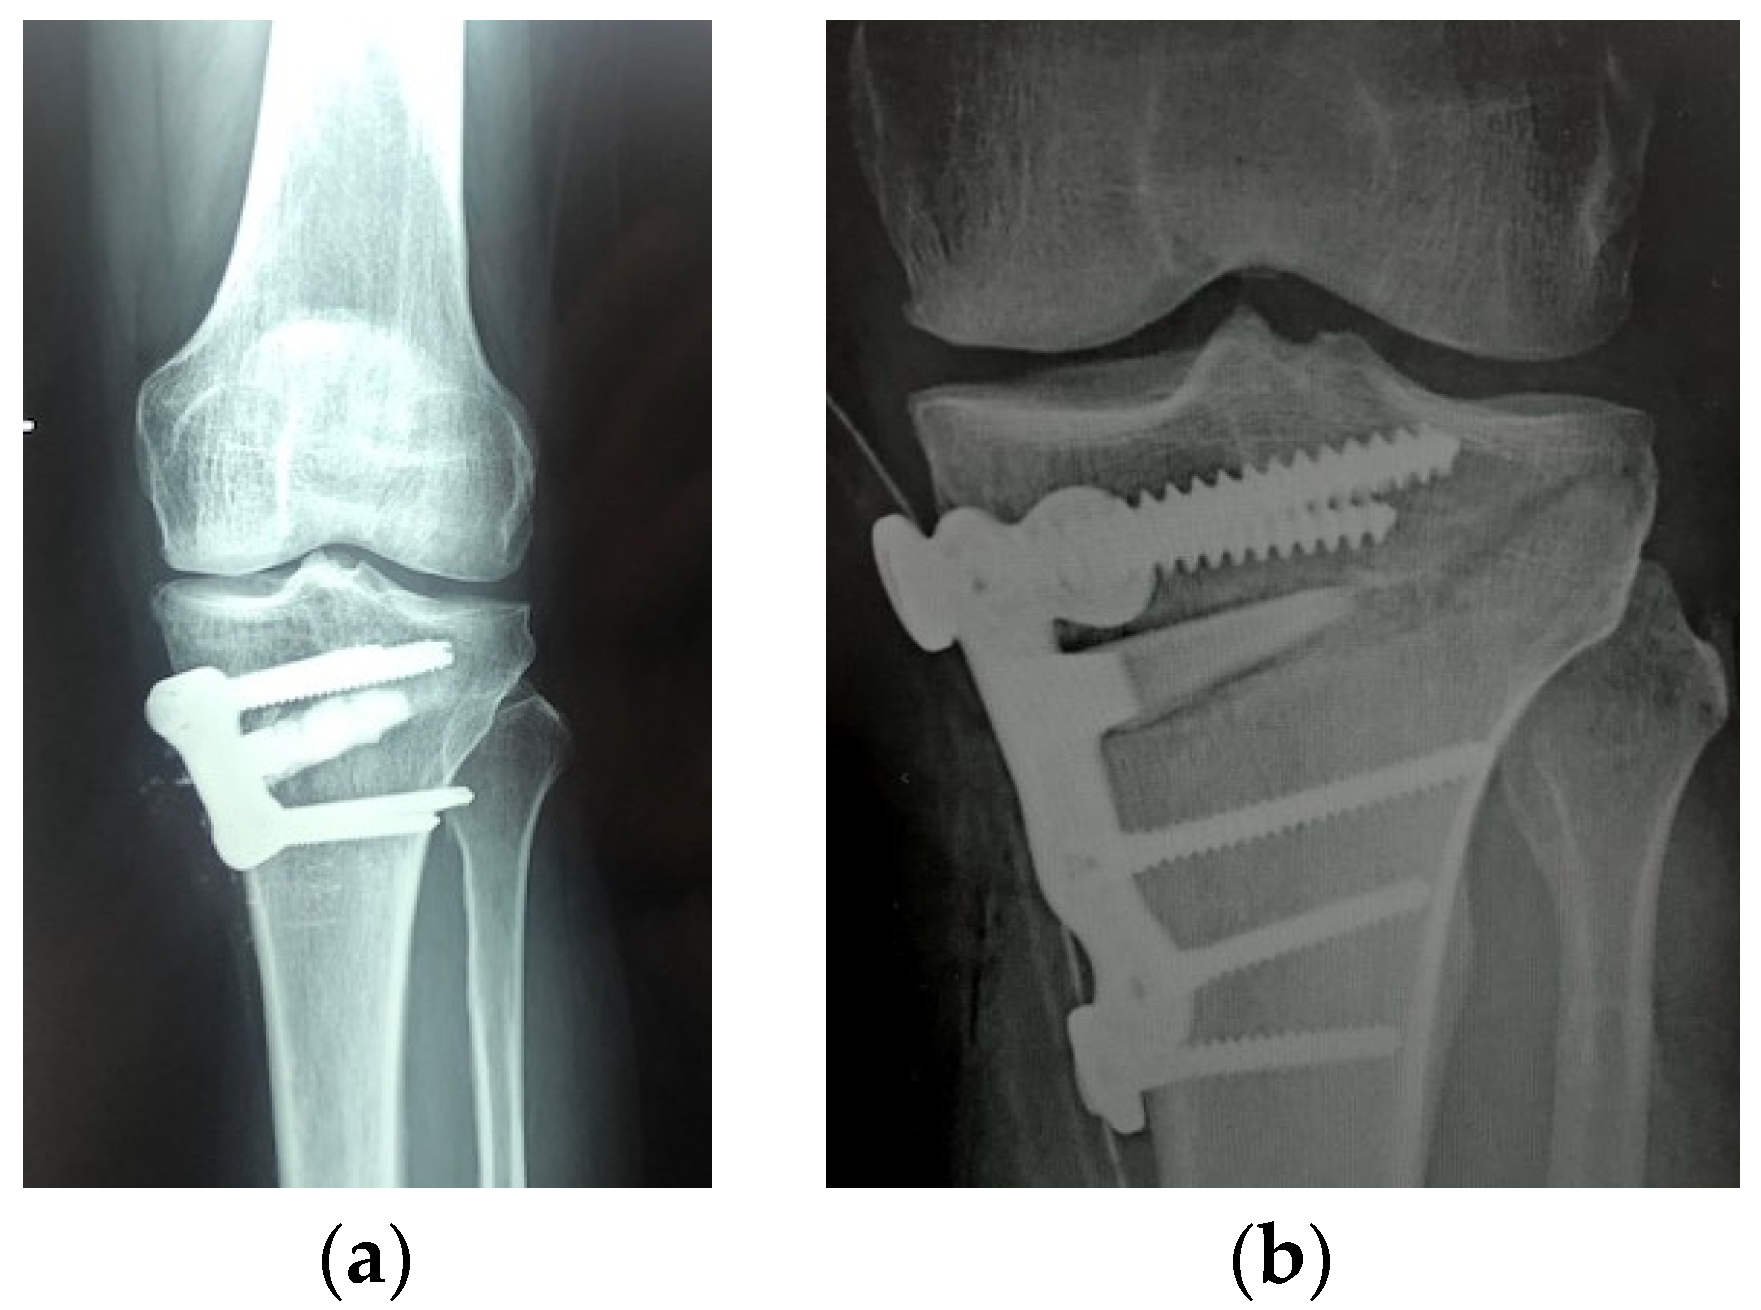

- El-Adl, G.; Mostafa, M.F.; Enan, A.; Ashraf, M. Biphasic ceramic bone substitute mixed with autogenous bone marrow in the treatment of cavitary benign bone lesions. Acta Orthop. Belg. 2009, 75, 110–118. [Google Scholar] [PubMed]

- Joeris, A.; Ondrus, S.; Planka, L.; Gal, P.; Slongo, T. ChronOS inject in children with benign bone lesions—Does it increase the healing rate? Eur. J. Pediatr. Surg. 2010, 20, 24–28. [Google Scholar] [CrossRef]

- Gómez-Barrena, E.; Rosset, P.; Gebhard, F.; Hernigou, P.; Baldini, N.; Rouard, H.; Sensebé, L.; Gonzalo-Daganzo, R.M.; Giordano, R.; Padilla-Eguiluz, N.; et al. Feasibility and safety of treating non-unions in tibia, femur and humerus with autologous, expanded, bone marrow-derived mesenchymal stromal cells associated with biphasic calcium phosphate biomaterials in a multicentric, non-comparative trial. Biomaterials 2019, 196, 100–108. [Google Scholar] [CrossRef]